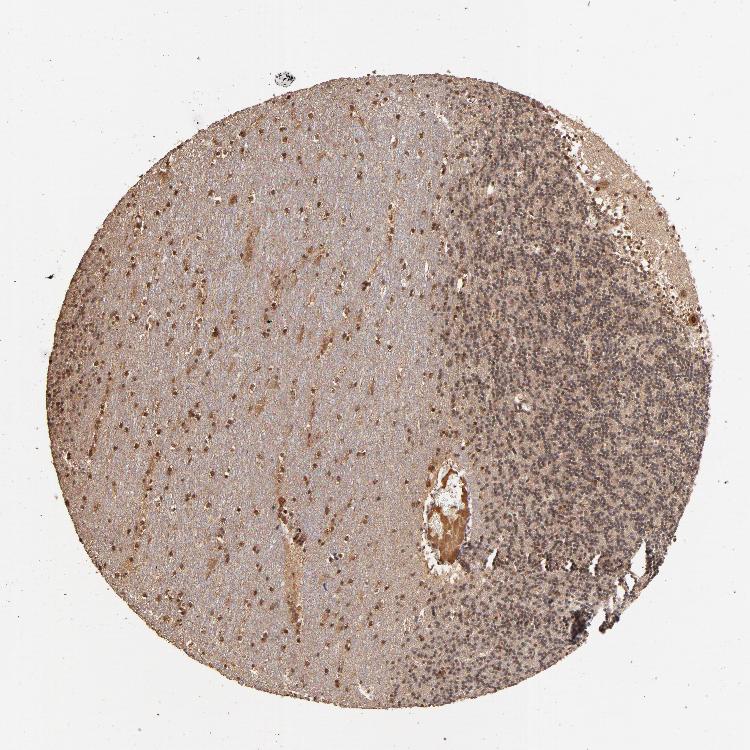

CEREBELLUM - Antibody stainingi

Antibody staining in the annotated cell types in the current human tissue is reported as not detected, low, medium, or high, based on conventional immunohistochemistry profiling in selected tissues. This score is based on the combination of the staining intensity and fraction of stained cells.

Each image is clickable and will lead to virtual microscopy that enables deeper exploration of all samples and also displays staining intensity scores, fraction scores and subcellular localization as well as patient and tissue information for each sample.

Antibody HPA002916

Purkinje cells Medium

Cells in granular layer Low

Cells in molecular layer Medium